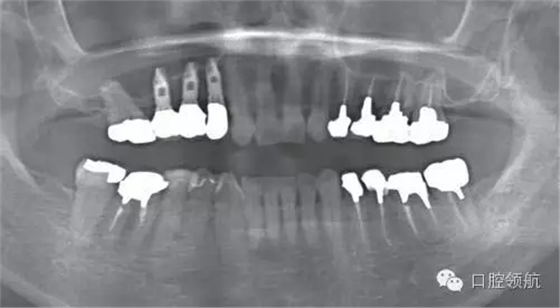

圖4 術后即刻的曲面斷層影像

圖5 術后2周愈合帽露出

術后1周準備拆線時,發(fā)現覆蓋螺絲部分露出。遂延期1周拆線,并每2天清洗一次創(chuàng)面,為了在暴露的覆蓋螺絲周圍有正常軟組織環(huán)繞,拆線后每隔2~3天來院,用生理鹽水清潔軟毛牙刷去除軟垢,保持創(chuàng)面清潔穩(wěn)定(圖6~圖10)。

圖6 術后周圍黏膜的變化。術后1個月的口內像

圖7 術后周圍黏膜的變化 術后4個月的口內像 種植體周圍未見炎癥表現

圖8 術后7年6個月的曲面斷層影像

圖9 治療結束后7年6個月的口內正面像